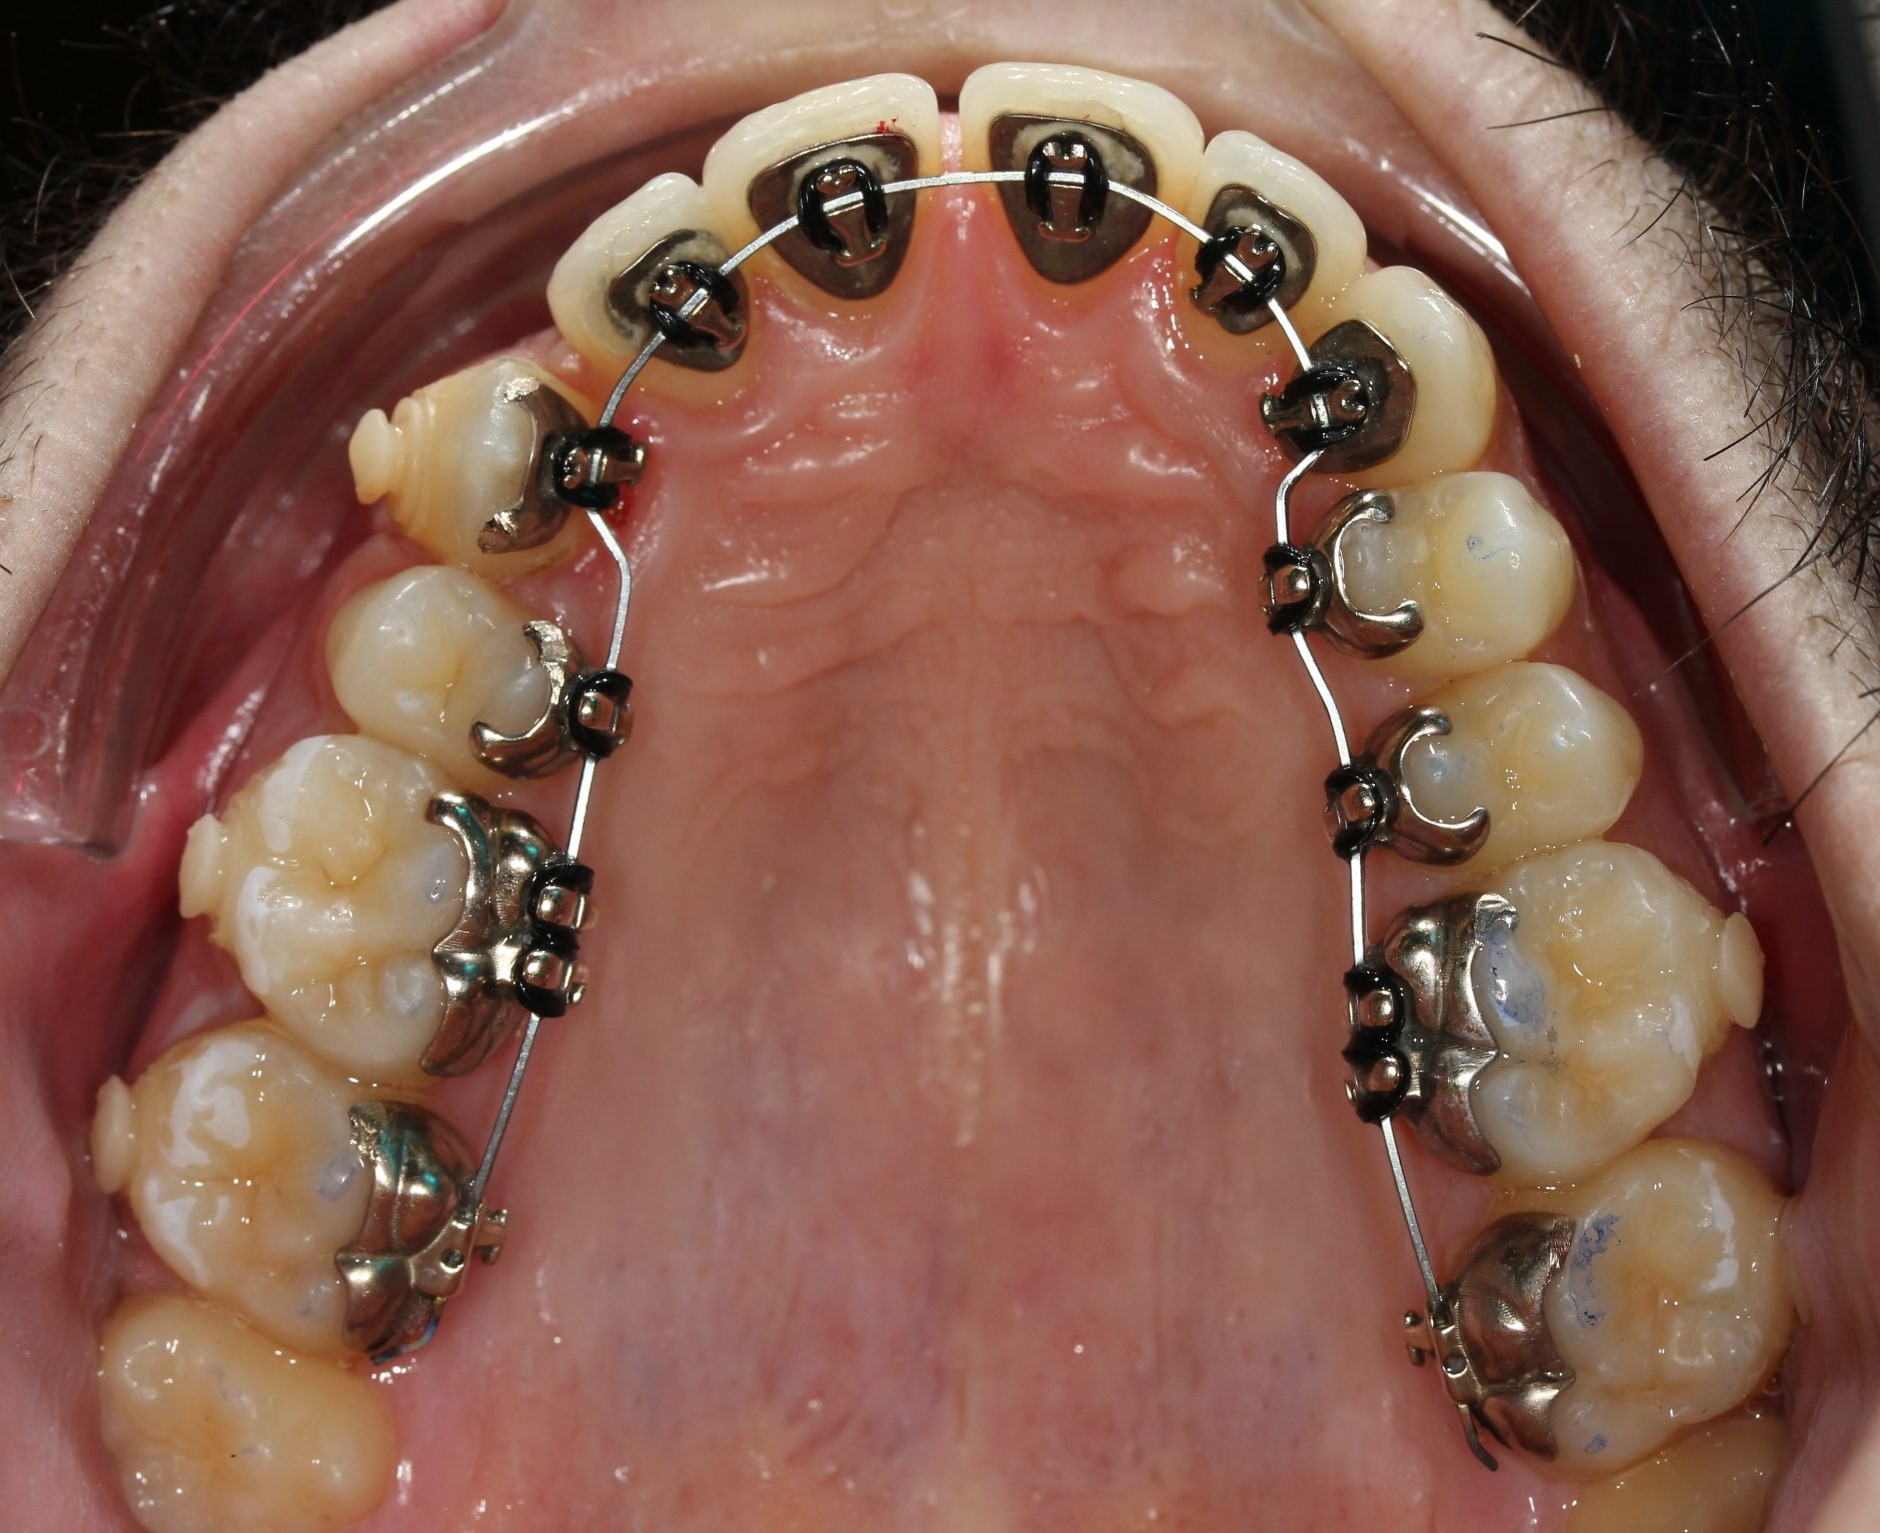

ORTODONCIA LINGUAL CON MICROTORNILLOS.

Paciente de 23 años que acude a la consulta con el fin de mejorar su sonrisa. Presenta Clase III, sobremordida 3/3 y retroinclinación de incisivos inferiores.

Ortodoncia lingual para alinear y nivelar arcadas.

Ortodoncia lingual.